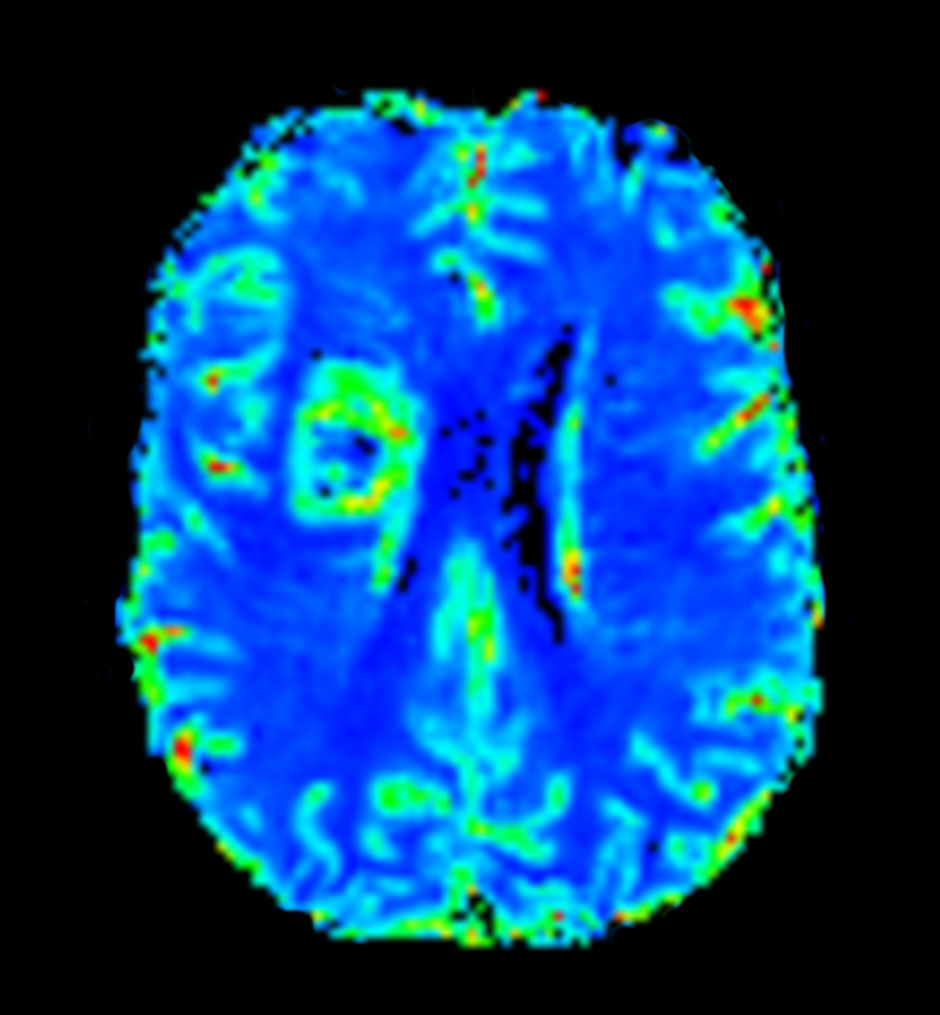

Axial T2* Perfusion (Index)

Axial T2* Perfusion (NI)